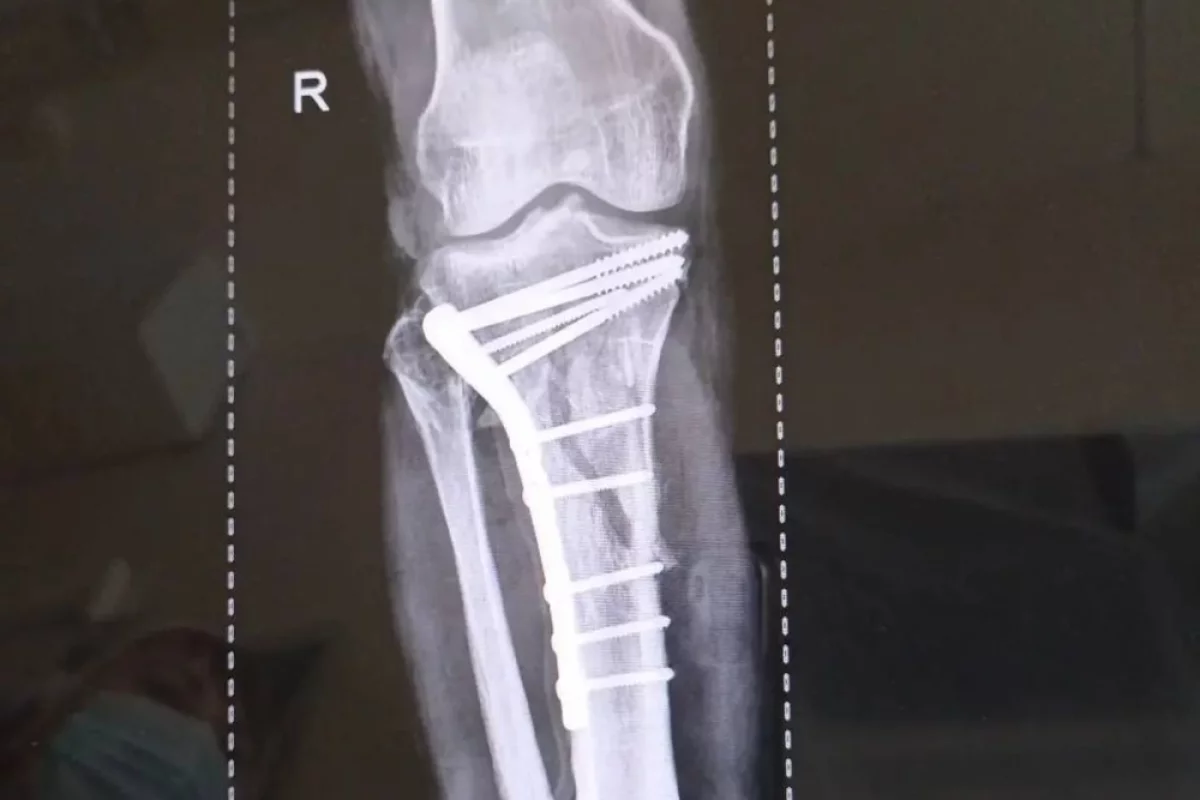

Липецкие врачи спасли ноги мужчины после страшного ДТП

В Липецке врачи-травматологи горбольницы «Липецк — Мед» спасли ноги мужчины после серьёзного ДТП. Об этом сообщили в пресс-службе областного Минздрава.

Пациент поступил после тяжелого ДТП 25 февраля. У него были внутрисуставные переломы верхних зон обеих голеней. Врачам потребовались почти три часа, чтобы по кусочкам собрать голени пострадавшего.

Оперировали заведующий отделением травматологии Дмитрий Соколов с ассистентом, врачом — травматологом Евгением Крюченковым. Специалисты оперировали одновременно обе ноги с минимальной кровопотерей. Сейчас пациента уже перевели из реанимации в отделение.